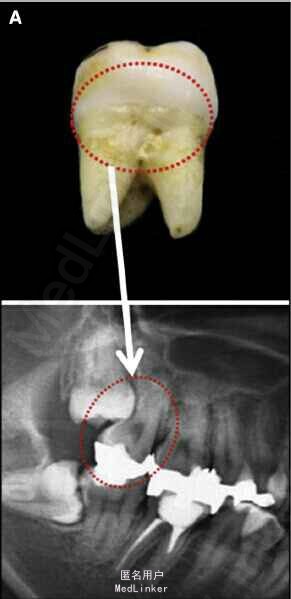

面部:凸面型,上下唇前突,上唇E线前3.5mm,下唇E线前9.5mm,闭唇时口周肌肉紧张。口内检查:双侧尖牙磨牙I类关系,左侧7锁合,覆盖4.5mm,覆合1mm,中线正,上颌拥挤度12.5mm,下颌拥挤度8.2mm。全景片示4个第三磨牙均阻生,怀疑上颌第二磨牙远中面因8阻生有牙根吸收,下颌8近中倾斜阻生更严重,右下6、左下4和5都行了RCT并大面积充填。头影测量示骨性I类,高角,下切牙唇倾。无TMJ症状,只是咀嚼测试时,右侧(非锁合侧)较左侧速度更快且更稳定。

诊断:安氏II类1分类,双颌前突,牙列严重拥挤,左下7锁合,双侧上7牙根吸收,四颗第三磨牙阻生 治疗目标:减少唇的突度及前牙拥挤,扶正4颗阻生的第三磨牙,达到良好的面部美观和功能咬合。 治疗:上颌拔除2颗5和2颗7(不拔4的原因为左上4为正常牙,左上5大面积充填;右上4形态较右上5好。因拔除了坏牙保留了健康牙齿,但是拔5不利于前牙的内收,所以于上后牙56之间植入了支抗钉加强支抗,辅助内收前牙。拔7原因为两颗7远中面均有牙根吸收且有大面积充填),下颌左侧拔除5和7(左下5根管治疗且根尖阴影,拔除左下7原因为严重锁合,改正困难且容易导致上下磨牙的伸长加重II类高角面型),右侧拔除根管治疗且大面积充填后的6;分别竖直4颗近中倾斜阻生的8,整个疗程39个月,四颗8成功的代替6或7。双侧I类尖牙关系,左侧磨牙I类关系,右侧磨牙完全远中关系。唇突度改善,全景片可见达到可接受的牙根平行度,4个8完全萌出直立。以前因为锁合导致的两侧咬合不对称没有了。

用阻生的第三磨牙代替缺损很大的磨牙是保留健康牙齿很有效的方法。患者1年后5个月随访,效果依然稳定。